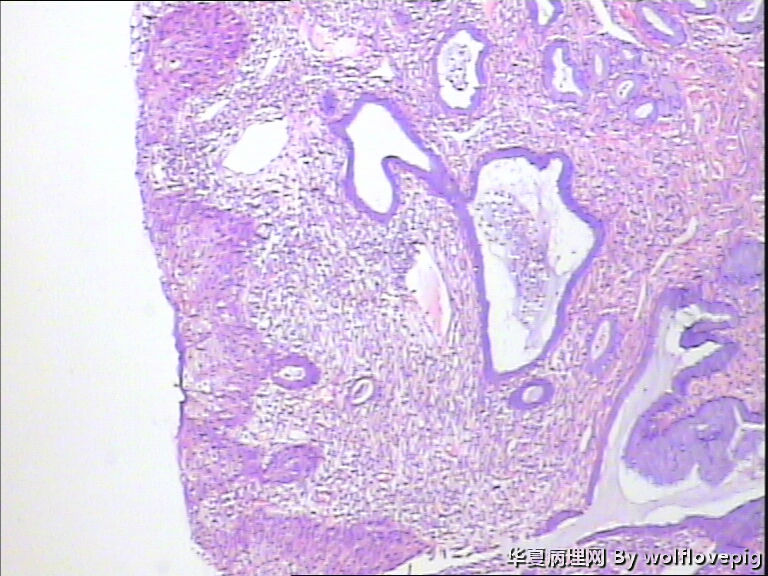

求助,宫颈!

37y

CIN3累腺

CINIII累及腺体

CIN2-3,累腺